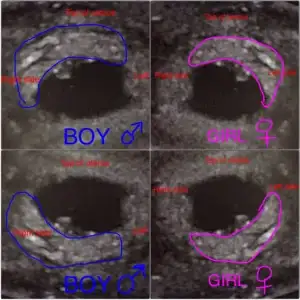

Ramzi teorisini düşünüyorum da, Embriyo ekranda sağ alt köşeye yaslanmıştı... elimizdeki örnekte acaba yine Sağa yatık mı çıkıyor, yoksa sağ sol farkı var mı? Buna göre cinsiyet nedir?

İnsallah daha net de gorursunuz bir sonraki randevuda. Sanirim plasentanin yonune gore yani bebegin saginda mi solunda mi olduğuna gore bakılıyor embriyo yönüne degil de